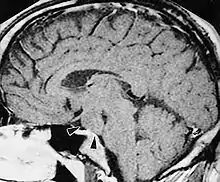

| A hypothalamic hamartoma (black arrows) on MRI | |

Tuber cinereum hamartoma is a benign tumor in which a disorganized collection of neurons and glia accumulate at the tuber cinereum of the hypothalamus on the floor of the third ventricle. It is a congenital malformation, included on the spectrum of gray matter heterotopias. Formation occurs during embryogenesis, typically between days 33 and 41 of gestation. Size of the tumor varies from one to three centimeters in diameter, with the mean being closer to the low end of this range. It is estimated to occur at a frequency of one in one million individuals.[1]

The tumor is difficult to detect by CT due to decreased sensitivity of the scan at the level of the sella turcica. MRI is the primary imaging modality for detection, with the lesion being of similar signal intensity to gray matter and non-enhancing with contrast. Lack of enhancement is an important imaging characteristic to help distinguish the tumor from similar masses that can occur in this region. These include germ cell tumors, granulomas of Langerhans cell histiocytosis and hypothalamic astrocytomas, as these lesions usually demonstrate at least partial uptake of contrast.[1]